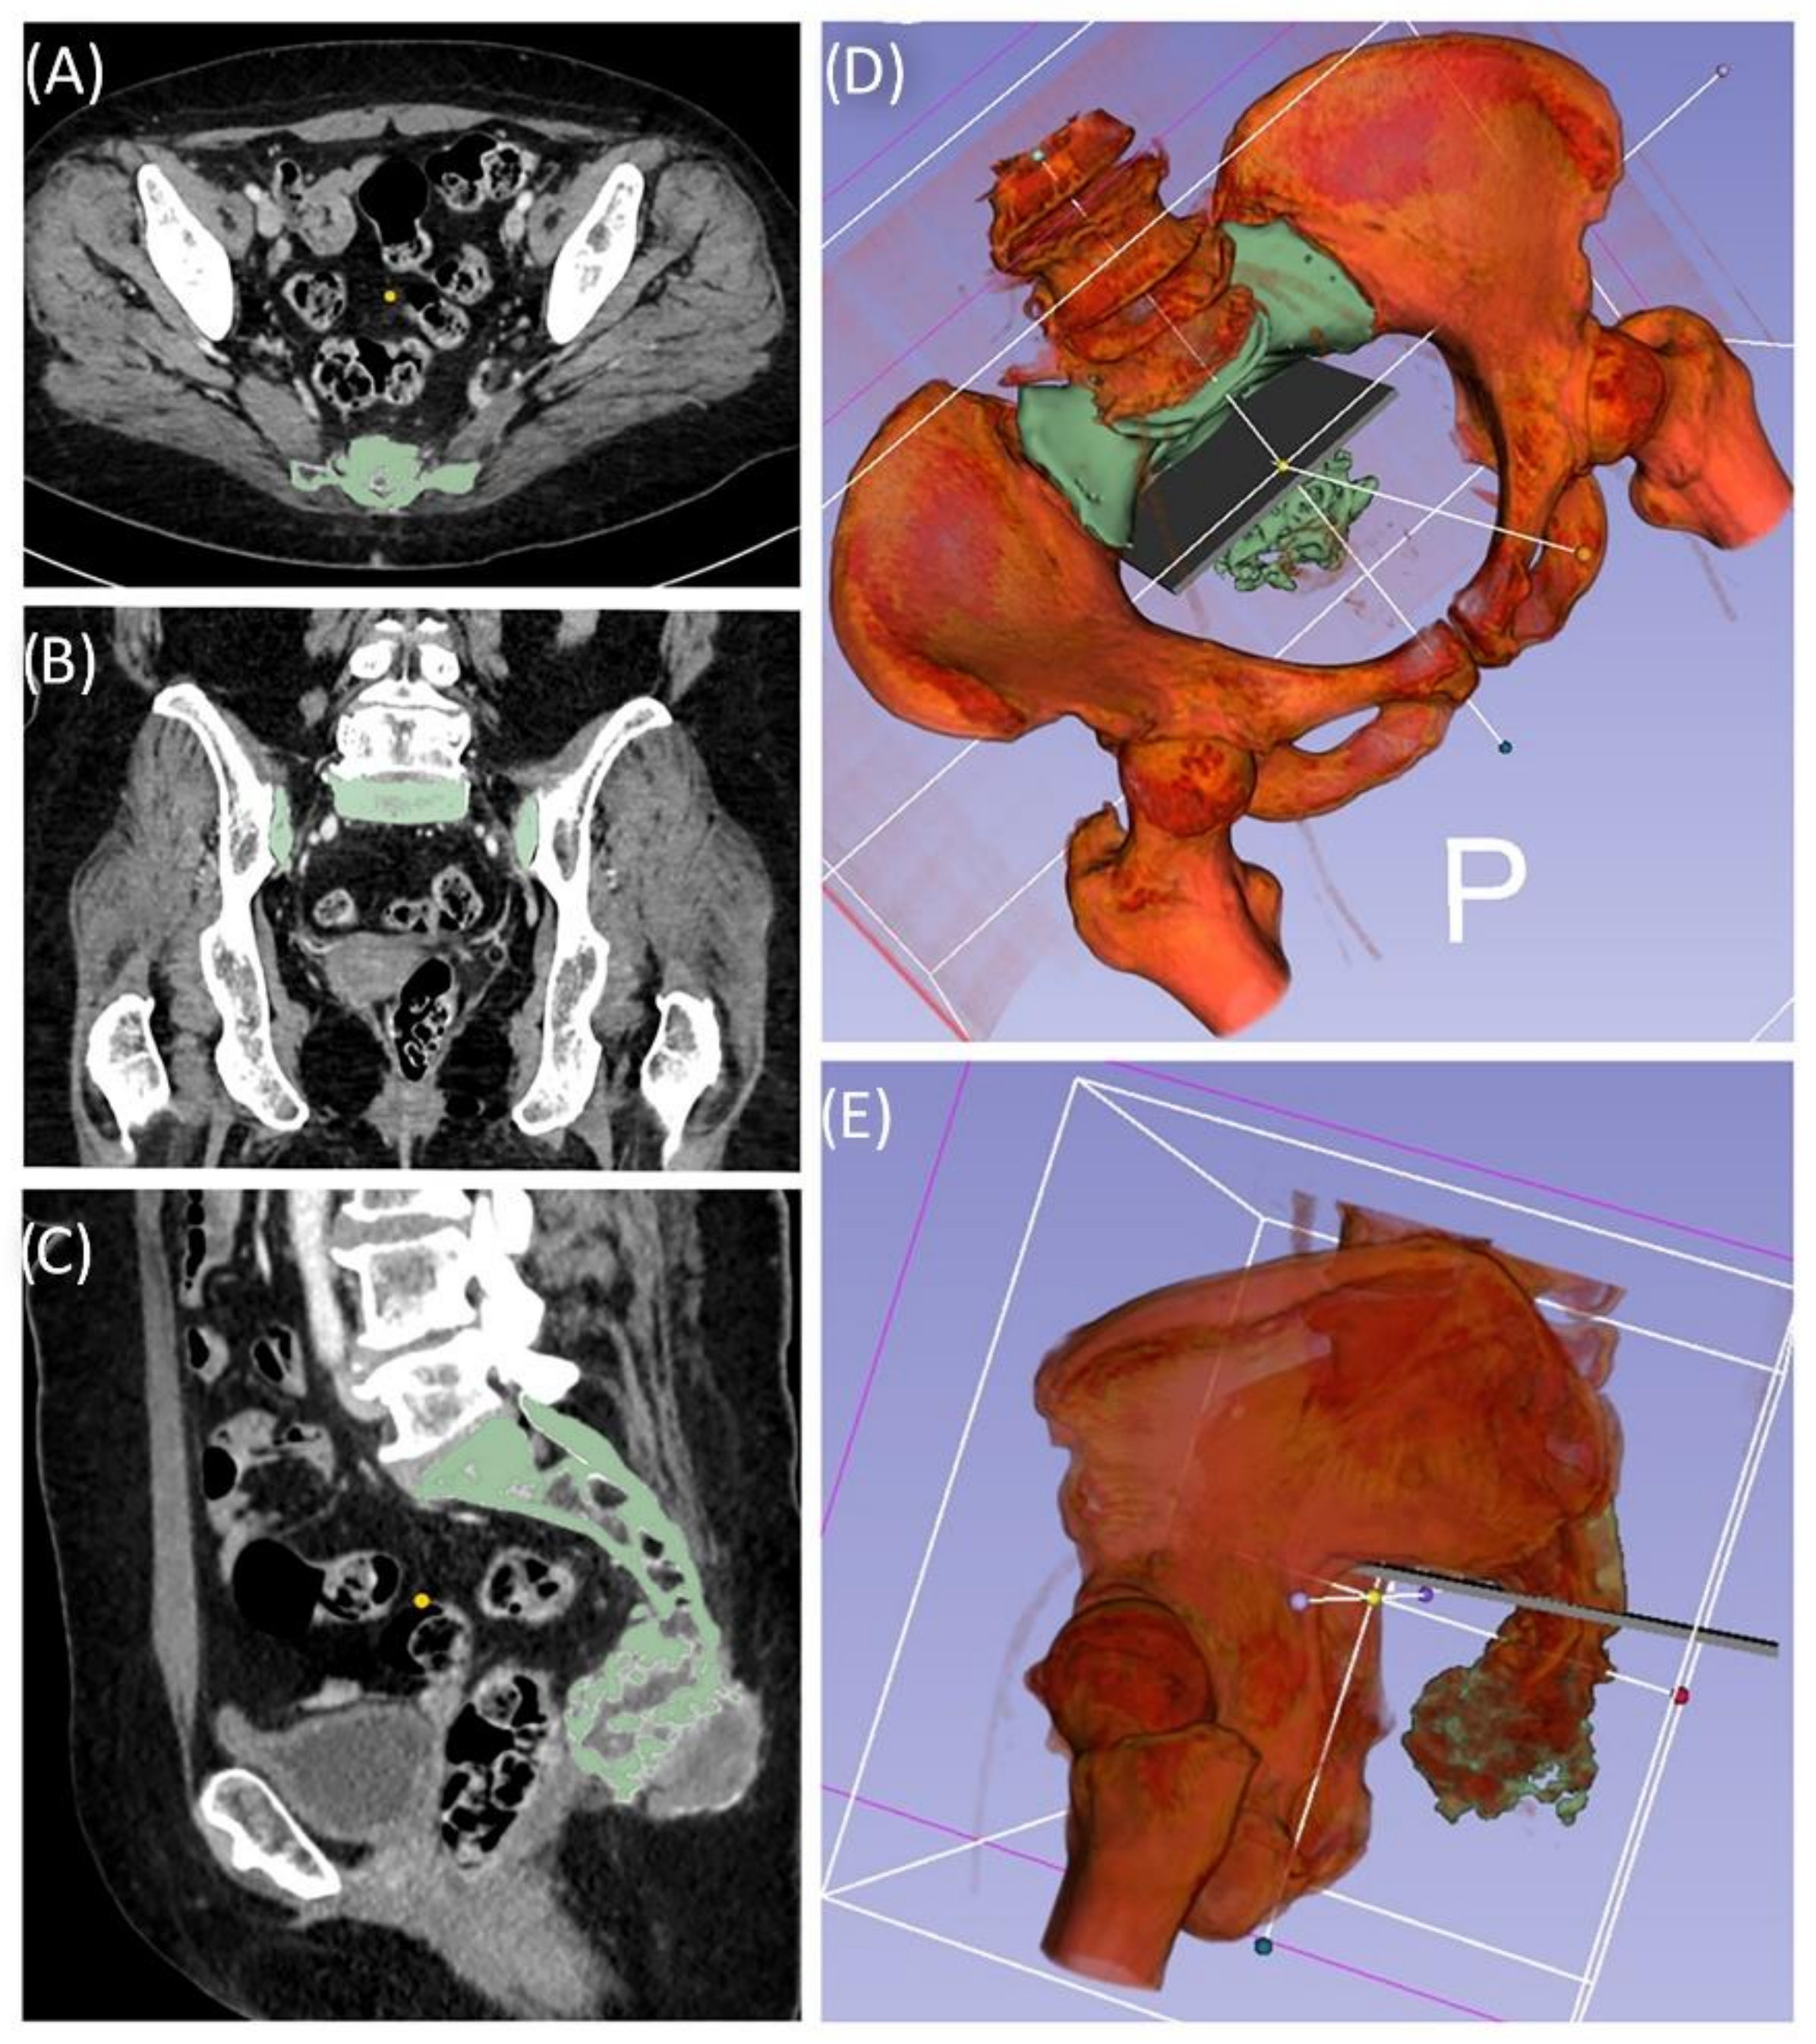

A 59-year-old female patient was diagnosed with bone metastasis of endometrial carcinoma of the sacrum with increasing and immobilizing pain. Primary radiation was discussed, but primary surgery and adjuvant radiation were preferred. Preoperatively, bladder/rectum dysfunction and a bladder-vaginal fistula were already present due to significant metastatic progression. The goal of 3D model-based planning and navigation was marginal resection of the metastasis in terms of a partial sacrectomy below S2 with ligation of the dural tube and the descending nerve roots below S2 (Figure 3 and Figure 4). Repeated revision surgery and systemic antibiotic treatment after wound infection were necessary. At the two-month follow-up, further metastases with pulmonary foci, which did not exist preoperatively, were found. Palliative treatment and radiation followed.

Figure 7. Case 4: Segmentation and resection plane planning of a high-grade osteoblastic osteosarcoma of the sacrum; cross-sectional segmentation (AC) and 3D model with the resection plane as the volume (gray) (D,E).